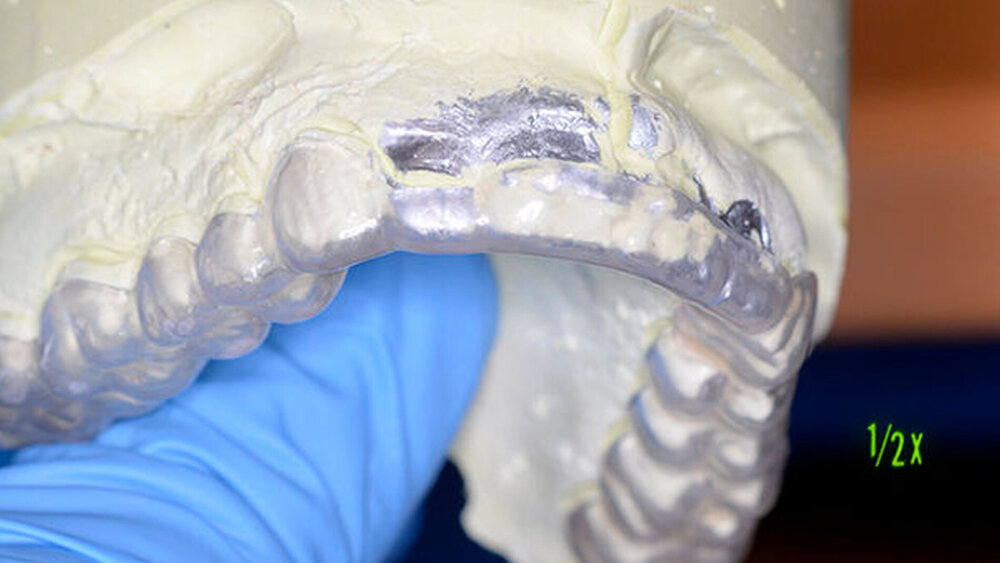

Der Zahn wurde zwei Stunden nach dem Unfall vital replantiert und semipermanent geschient. Die anschließende Abdrucknahme erfolgte unter allergrößter Sorgfalt. Die laborgefertigte Tiefziehschiene schließt die Bereiche der semipermanenten Schiene bis zum Schienenäquator mit ein. Was die Reanastomosierung der Gefäße und Nerven betrifft, ist der Behandler zuversichtlich, reagieren doch auch vital transplantierte Weisheitszähne nach einigen Wochen wieder auf Kältereize.